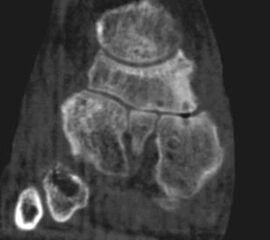

Abbildung 2.1.

Bildbeispiele symptomatische OCL

Zum Lesen der Bildbeschreibung und zur Vollansicht bitte das Bild anklicken. Bild: H. C. Rischke

Abbildung 2.2.

Bilder eines Patienten mit Z. n. mehrfachen Sprunggelenksdistorsionen in der Vergangenheit, besonders heftige Distorsion des linken Sprunggelenkes 5 Wochen vor der Untersuchung. Die SPECT/CT zeigt eine instabile osteochondrale Läsion mit deutlicher Aktivierung.